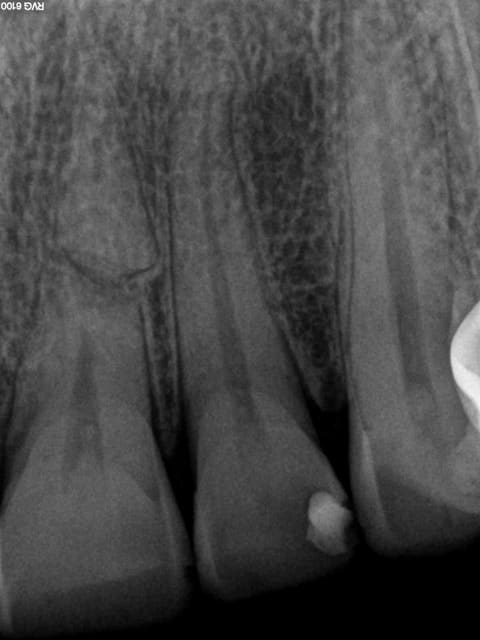

Bien sur dans les secteurs antérieurs,selon la HAS, jamais les radios ne sont justifiées hors signes d'appels. A l'instant : aucune douleur, ras vous ne trouvez pas. ? -))))

1 rdscif - Eugenol

X ray 03 medium zvq18j - Eugenol

4a338550 6a5b 47ea b2a7 d3cb675c5076 oni5gh - Eugenol

fistule69

13/10/2014 à 23h02

Bonsoir Chicot,

Comment tu gères ta préparation sous gingivale sans saignements ?

Merci et à bientôt !

😉

Capture d  cran 2015 03 12 12.28 - Eugenol

chicot29

13/10/2014 à 23h57

Anesthésie, fraise fine, Bistouri électrique + expasyl.

Tapez pas trop fort ! -))))